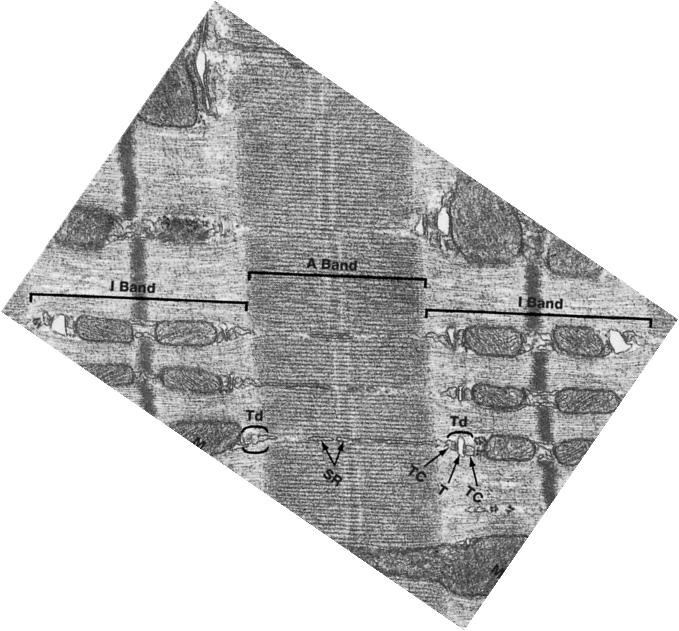

What are the arrangements of contractile proteins in striated muscle?

The sarcomere is the lowest functional unit of skeletal muscle that is arranged in parallel. They are separated by Z lines.

Z lines are where actin filaments are anchored and provide structural support, effectively maintaining the organization of the sarcomere during muscle contraction.

The M line runs straight through the midpoint of the myosin filaments.

What is the relationship between T tubules and the sarcoplasmic reticulum?